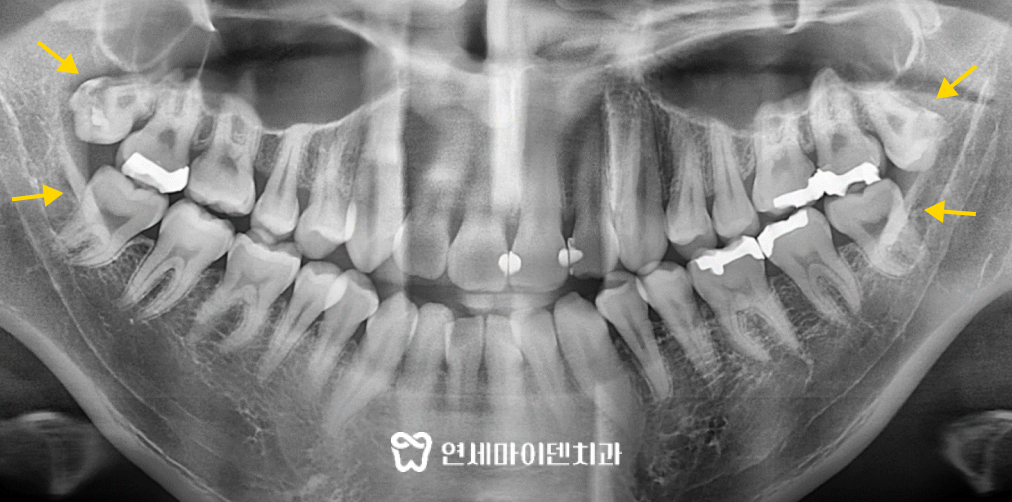

파노라마 방사선 촬영으로 구내 상태를 더 면밀히 확인해보면,

아래 앞니는 삐뚤게 배열되어있고,

사랑니 4개 모두 과맹출 된 상태였습니다.

약간의 잇몸 퇴축이 확인되기는 했지만,

다행히도 전체적인 잇몸 상태는 양호한 편이었습니다.